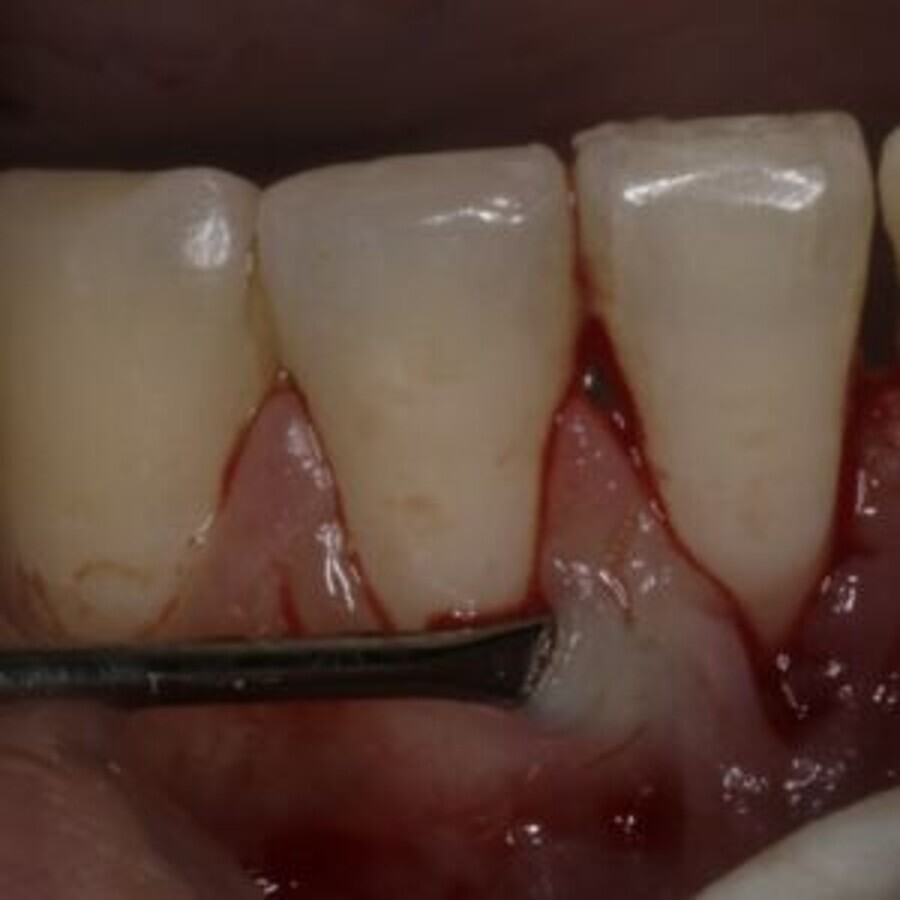

Fig 2: De-epithelized Free Gingival Graft

The techniques used to harvest the connective tissue graft have also evolved towards procedures that do not involve healing by secondary intention and minus vertical incisions. The various procedures are the trap door technique with vertical incisions (Edel 1974), The double incision technique ( Langer and Calagna, 1982) The envelope technique (Raetzke, 1985) (Langer and Lager 1985), and the single incision technique (Hurzler and Weng, 1999). The de-epithelized Free gingival graft ( Zucchelli et al., 2003) remains the only modern technique that has gone against the flow and involves healing by secondary intention.